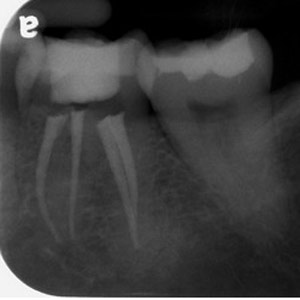

NON-SURGICAL

Oftentimes, our patients need non-surgical treatments that require minimal intervention. This intertwines with our belief that preventative maintenance and regular dental care can minimize the need for surgeries. You can rest assured that our highly trained and experienced team consistently provides the highest quality endodontic treatments and assistance available in the North Shore.